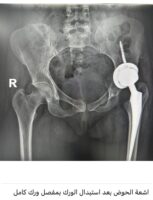

مضيفاً : وصلت المريضة للمستشفى وتم إجراء كافة التحاليل والفحوصات والإشاعات المطلوبة و التي أكدت إمكانية إجراء عملية تغيير مفصل كامل للورك بأمان رغم صعوبة التغيرات العظمية للورك وضمور العضلات وقصر الرجل وتمت العملية بنجاح ولله الحمد لتضاف للجراحات النوعية في جراحة استبدال مفصل الورك التي تتم في المستشفى ،وتؤكد على تطور الخبرات الطبية بالمستشفى بأحدث التقنيات الطبية الحديثة المتطورة عالمياً.

واختتم العتيبي حديثه مشيراً إلى أن المريضة بدأت في مرحلة التأهيل لاستعادة الحركة بدون ألم بمفصل ورك صناعي كامل.